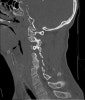

CT : 경추 골절(Fractures of the Cervical spine)

AP, lateral, open-mouth view를 모두 찍습니다(C2). 다발성 손상환자에서 가장 중요한 X-ray는 C1~T1까지 다 볼 수 있는 cross-table view X-ray 사진입니다. 대부분 CT나 MRI도 필요합니다.

가장 잘 놓치는 손상 부위는 상부 및 하부 목뼈부위 손상이므로 lateral X-ray에서는 위로는 후두부, 밑으로는 T1까지 촬영하여야 합니다. 가끔 목뼈-등뼈 연결부위를 보기 위해 수영면(swimmer's view) 영상을 필요로 하지만, 대개 이 부위는 CT나 MRI로 평가합니다.

골절이 없더라도 척추 불안정 징후(추체가 인접 추체에 비해 3.5mm 이상 혹은 11º 이상 전위)가 있나 유심히 살펴보아야 합니다. 필요시 목의 flexion-extension X-ray 검사를 추가합니다. 척추 주위 근육의 경축이 심하면 flexion-extension 사진에서 인대의 불안정성이 잘 나타나지 않을 수 있으므로 CT나 MRI가 필요할 수 있습니다.